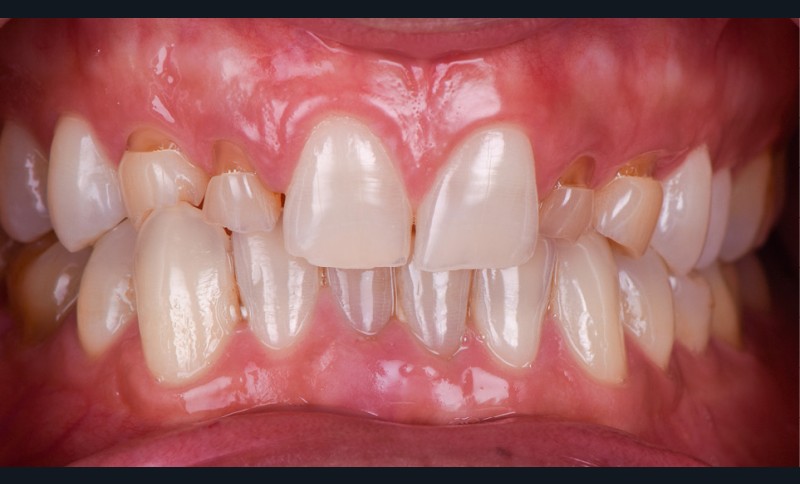

Un homme de 38 ans se présente en consultation d’implantologie pour le remplacement de ses 4 dents lactéales 52 53 62 63. Il ne présente pas d’antécédents médicaux, chirurgicaux, pas d’allergie, est non-fumeur. L’analyse clinique, radiologique et préprothétique fait apparaître (fig. 1) :

- les agénésies de 12 13 22 23 46 ;

- des usures marquées des bords libres des dents lactéales ;

- une égression compensatrice de certaines dents antérieures mandibulaires ;

- un parodonte sain et épais.